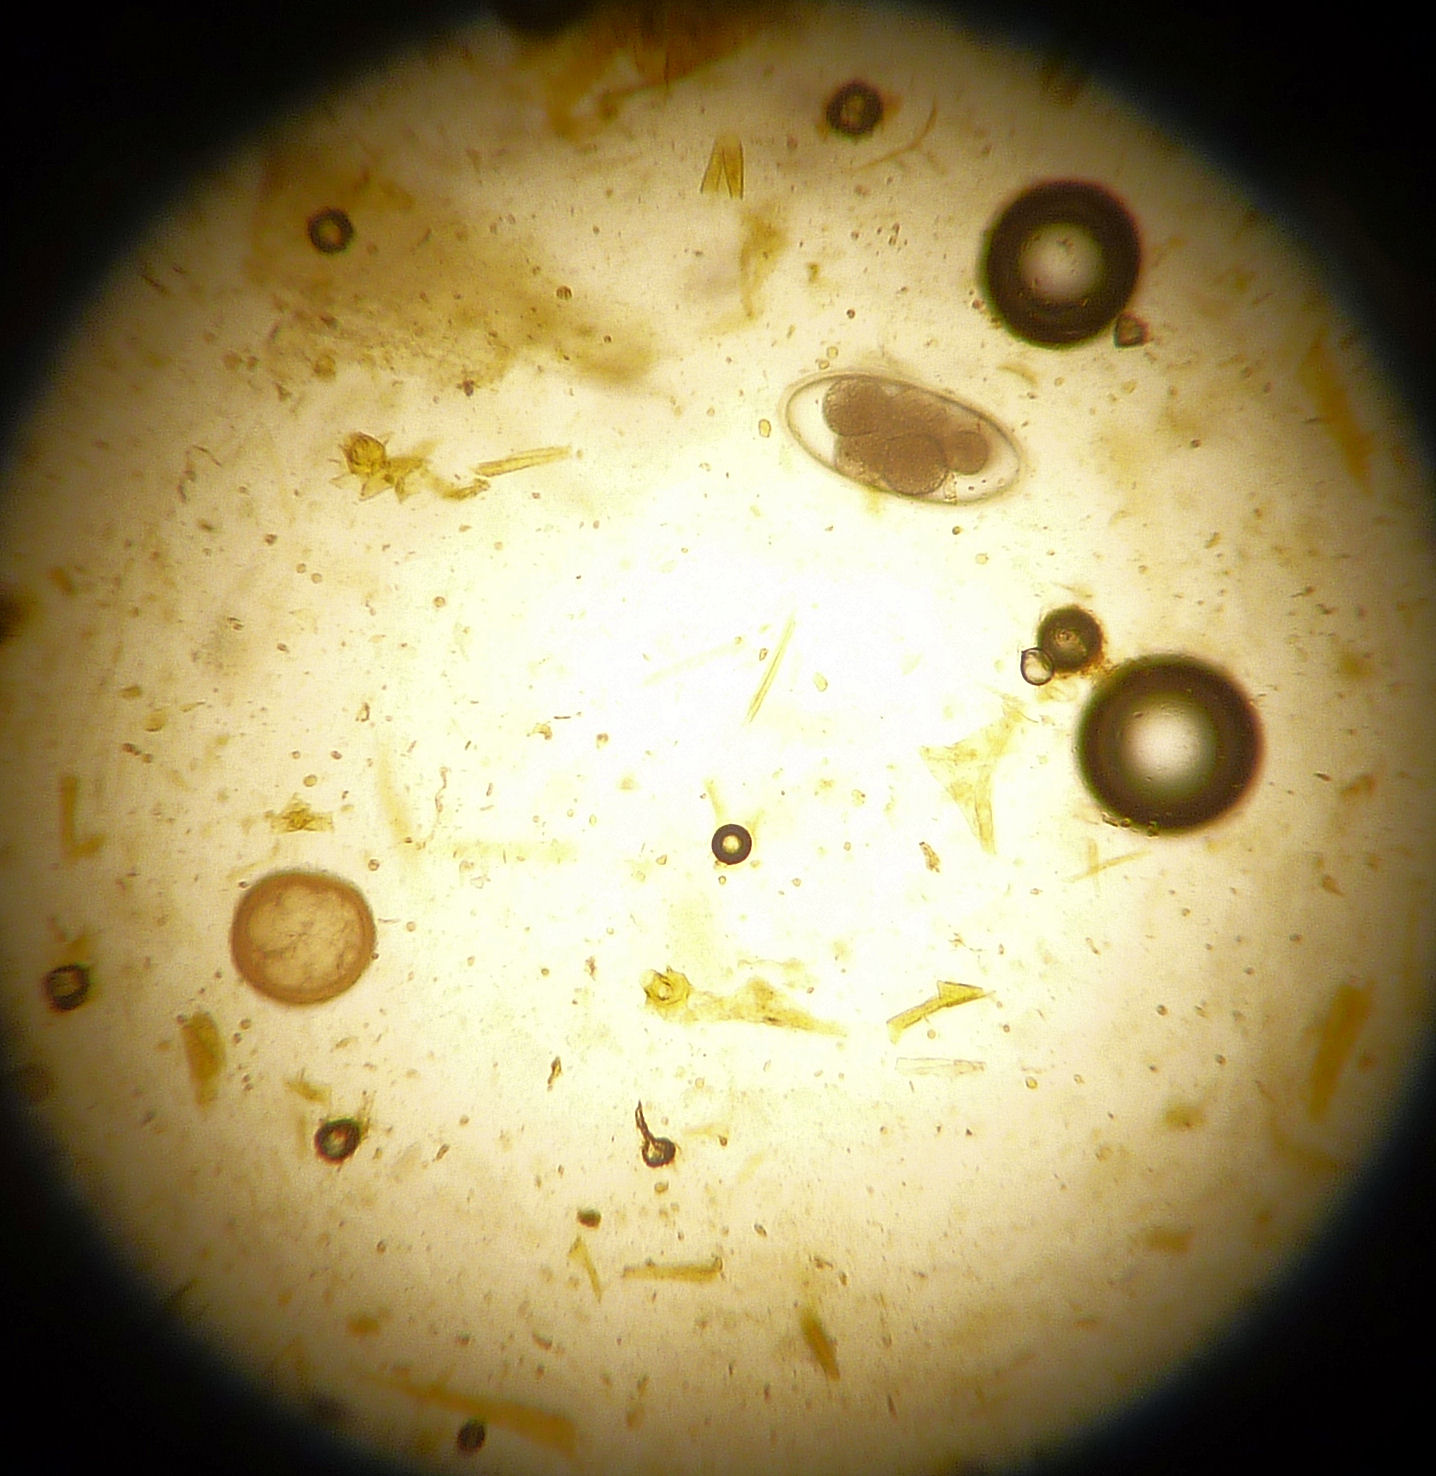

Fecal Exams

images/Nematode.jpg

images/coccidia.jpg

images/P1000736.JPG